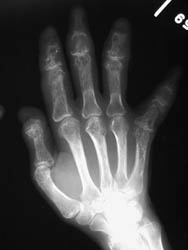

The hands are the most common site of osseous involvement. The middle and

distal phalanges and less frequently the proximal phalanges and metatacarpals

may show changes associated with sarcoidosis. Involvement at the wrist occurs

much less frequently.

An abnormal trabecular lace-like pattern of destruction can often be seen

at the phalanges and metacarpals of the hands. Cystic changes and osseous

destructive lesions may also be evident. Acro-osteosclerosis with the radiographic

appearance of terminal phlangeal sclerosis is not specific; however, it has

been reported in up to half of the patients with skeletal abnormalities of

sarcoidosis. Soft tissue swelling, and inflammatory skin nodules (erythema

nodosum) are occasionally noted. If the wrist is involved, cystic changes

and lytic lesions may be present.

The abnormal trabecular pattern of destruction at the hands is fairly characteristic of sarcoidosis. If osseous destruction is present at the distal phalanges, the appearance may be similar to findings associated with scleroderma. However, scleroderma has fairly characteristic associated soft tissue findings which distinguish it from sarcoidosis.